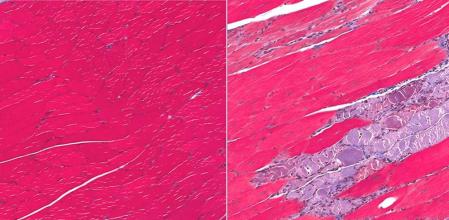

La causa de esta enfermedad radica en la mutación de algunos genes. El ser humano tiene algunos genes que son fundamentales para la generación de proteínas que actúan como protectoras de las fibras musculares. Cuando alguno de estos genes muta y no cumple su función aparece la distrofia muscular. La mayor parte de estos genes mutantes se transmite hereditariamente.